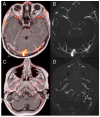

Results: A 6-year-old patient was admitted for right otomastoiditis and thrombosis of the sigmoid and transverse sinuses, as well as the proximal portion of the internal jugular vein. Radiological examinations revealed a left orbital mass (22 × 14 mm) compatible with asymptomatic orbital meningocele (MC) herniated from the superior orbital fissure (SOF). The child underwent a right mastoidectomy. After the development of symptoms and signs of intracranial hypertension (ICH), endovascular thrombectomy and transverse sinus stenting were performed, with improvement of the clinical conditions and reduction of the orbital MC. The systematic literature review encompassed 29 publications on 43 patients with spontaneous orbital MC. In the majority of cases, surgery was the preferred treatment.